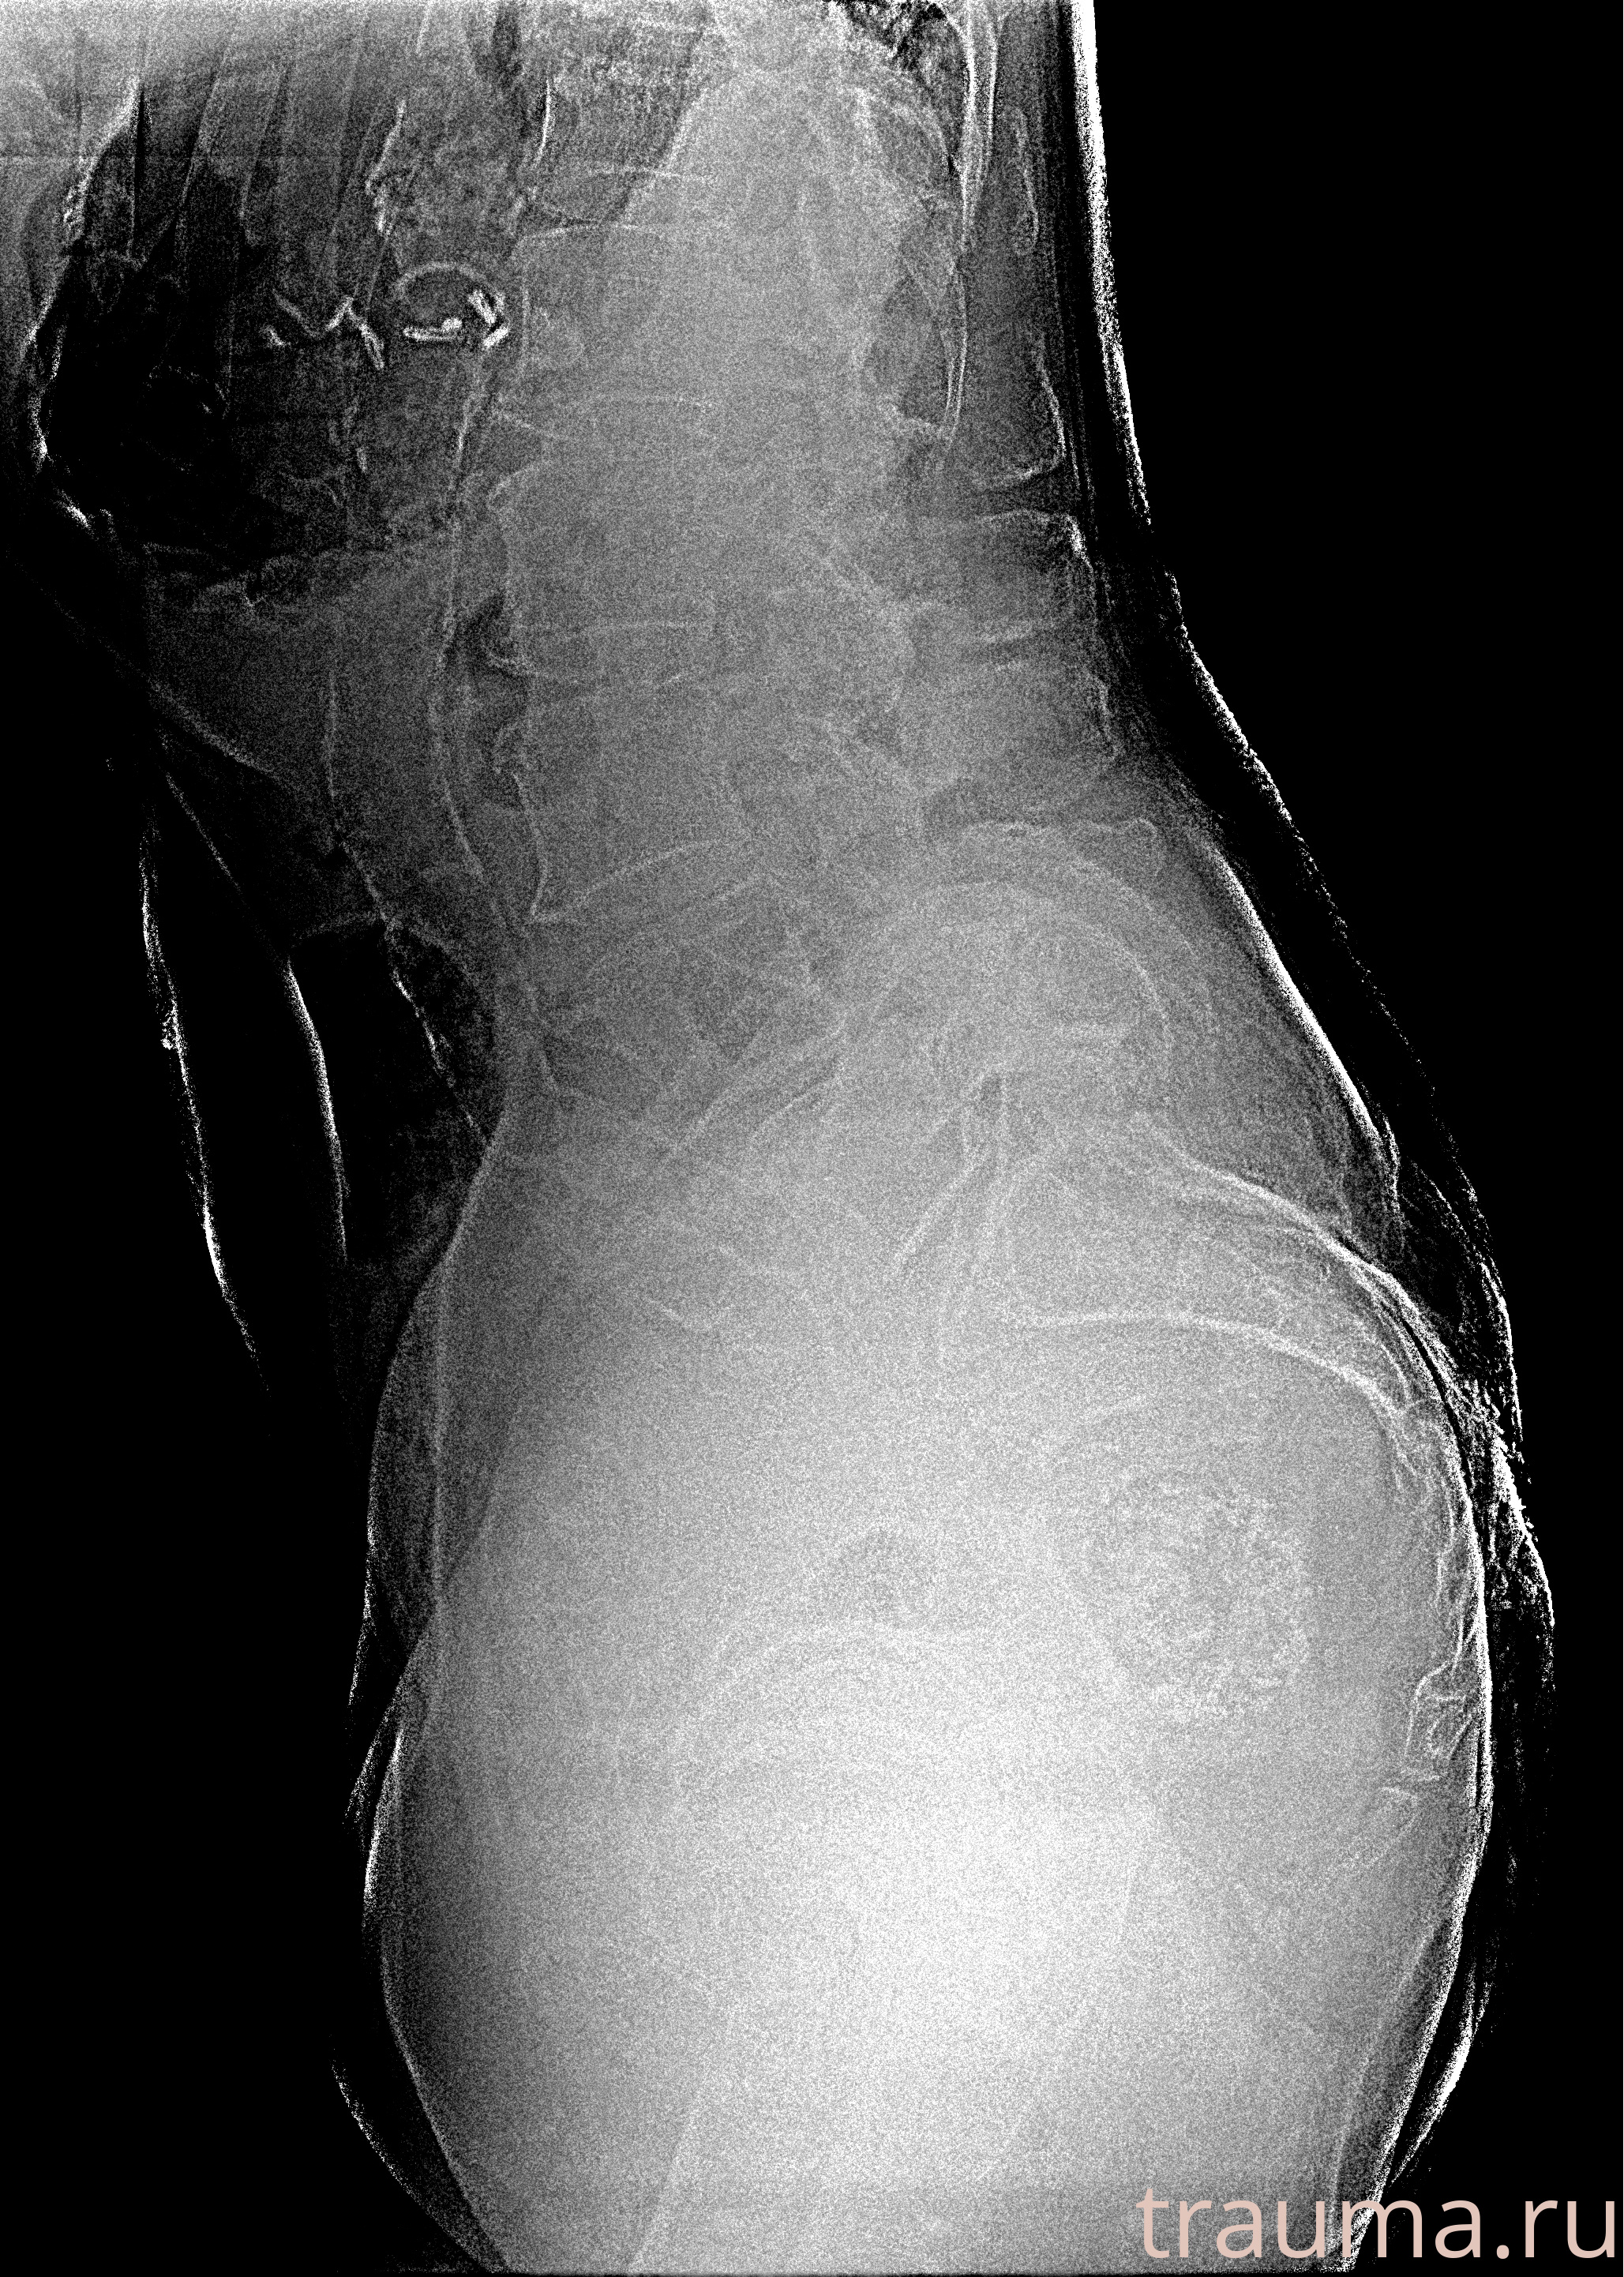

Рентгенограммы

Рентген на дому: по вашему адресу приезжает врач-рентгенолог, травматолог-ортопед с мобильным рентгеновским аппаратом, проводит диагностику травмы или заболевания, делает необходимые рентгенограммы, дает рекомендации по дальнейшему лечению. Получить качественные снимки в домашних условиях возможно благодаря уникальной методике, разработанной МосРентген Центром для института  Склифосовского